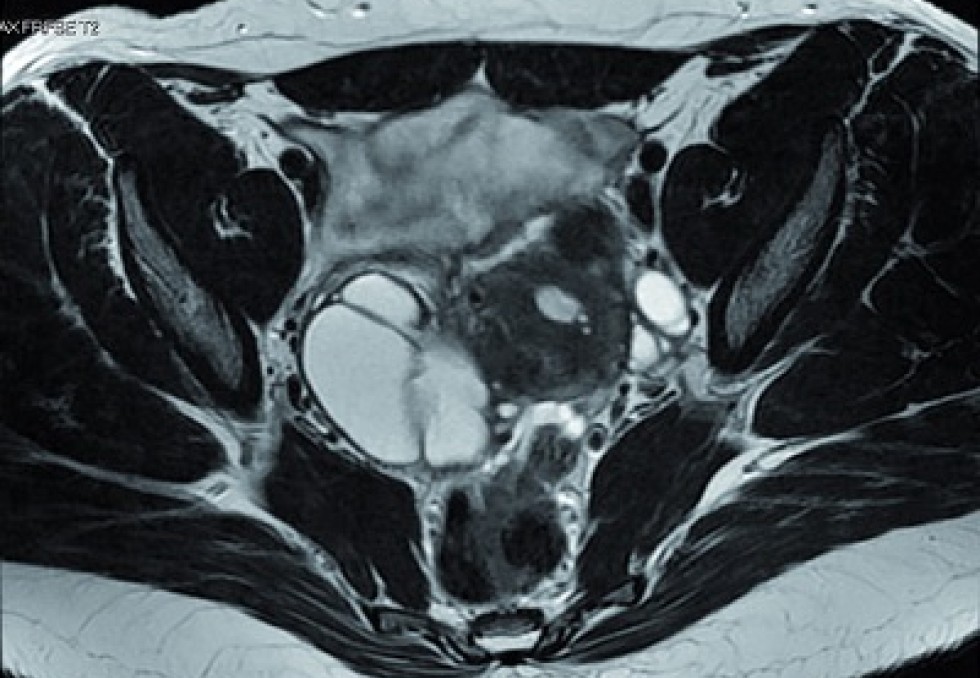

Une étude, nommée Endobest, portant sur 2 500 patientes, désormais toutes déjà recrutées, sera présentée à l'autorité. Elle a pour objectif d'"évaluer l'impact de Ziwig Endotest sur la décision médicale et la prise en charge des patientes présentant des douleurs pelviennes chroniques invalidantes, fortement évocatrices d’endométriose, mais avec un bilan d’imagerie de référence négatif ou incertain", précise Ziwig dans un communiqué daté du 20 janvier. Ainsi, les conditions d’utilisation de l’Endotest restent restrictives puisque le test ne peut être prescrit qu'à des patientes pour lesquelles le diagnostic d’endométriose reste incertain malgré l’imagerie.